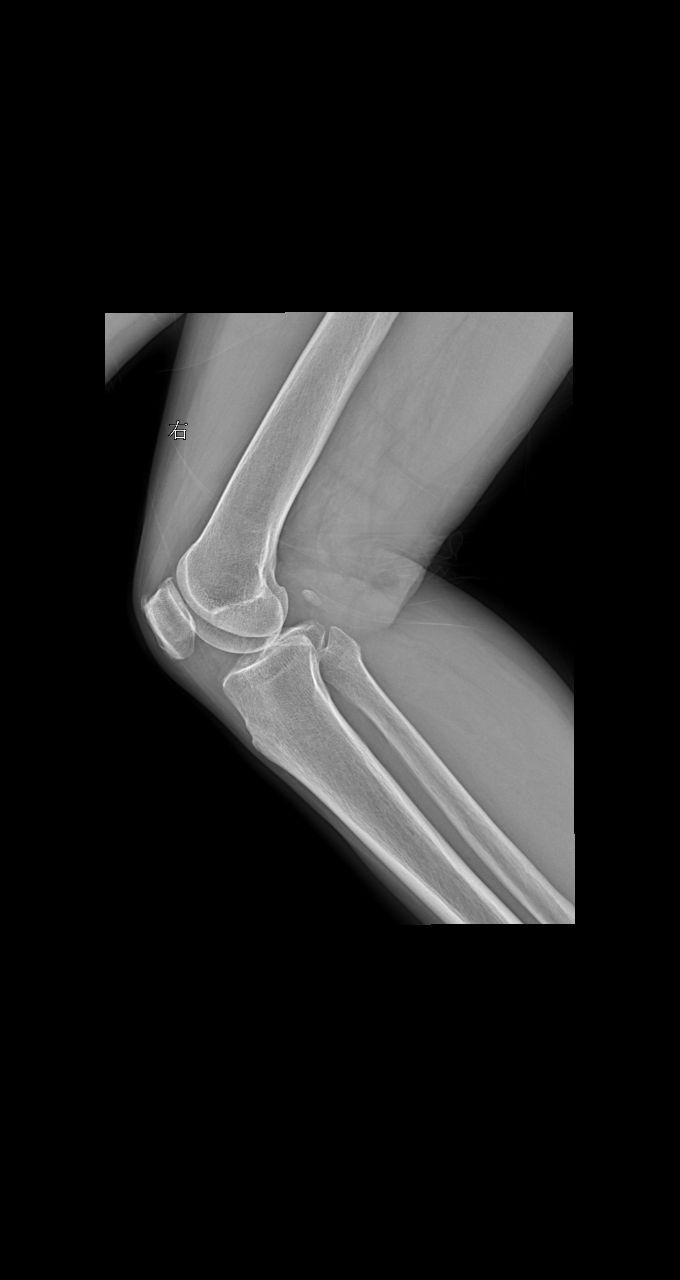

老师们拍摄膝关节采取站立位还是卧位